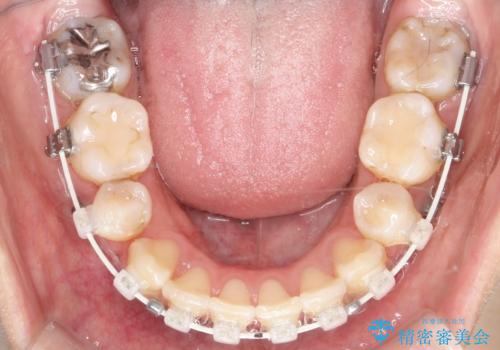

- 口元が出ていることを気にされて来院されました。精密な検査の結果、歯列全体のスペースが不足していることが判明。患者様のご希望である「口元を下げたい」というご要望を叶えるため、上下左右の小臼歯を抜歯し、そのスペースを利用して前歯を奥へ移動させる治療計画を立案しました。また、仕事上、目立つ矯正装置を避けたいというご希望から、上顎に裏側矯正、下顎に表側矯正を組み合わせたハーフリンガル矯正を提案しました。

今回の矯正治療では、口元を大きく下げるため、上下左右の小臼歯を抜歯しました。装置には、上顎は歯の裏側に装着する裏側矯正(舌側矯正)を、下顎は透明で目立ちにくい審美ブラケットを使用するハーフリンガル矯正を選択。これにより、治療中も他人の目を気にすることなく、ストレスなく過ごしていただけました。抜歯によってできたスペースを有効活用し、歯列全体を後方へ移動させることで、口元の突出感を解消。治療の結果、口元がすっきりと整い、自信のある美しい横顔を獲得していただけました。